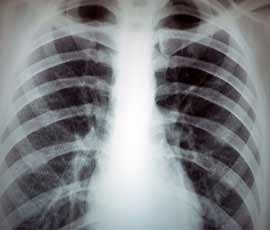

Attacks of wheezing caused by viral infections in the upper respiratory tract are common in preschool children between the ages of ten months and six years. Preschool children who visit hospital with such symptoms are commonly treated with a short course of prednisolone - a steroid which is used to reduce inflammation in the airway and which is very effective in treating attacks of allergic asthma in older children and adults.

It has recently been recognised that wheeze in most preschool children is only triggered by viral colds, and is therefore a different condition from ‘allergic asthma’. There is conflicting evidence whether a short course of oral prednisone is effective in this age group.